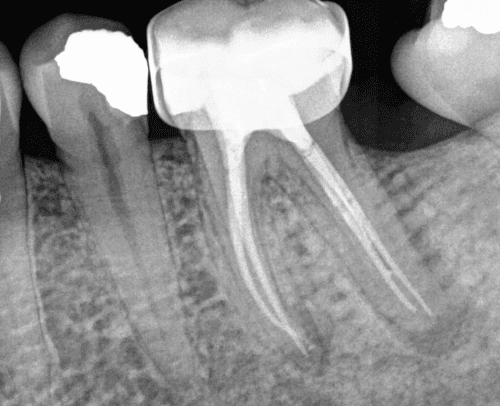

KREENA'S CASES